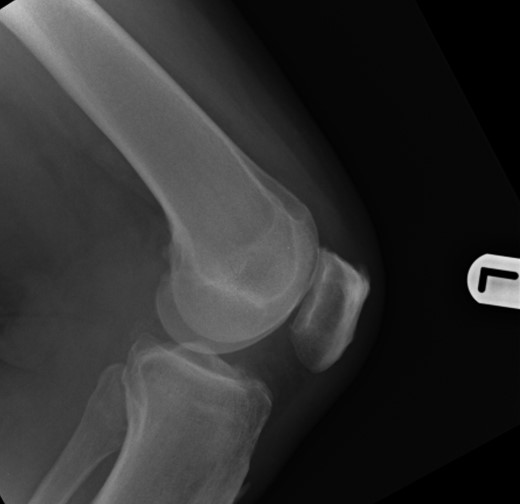

Repeat radiographs performed by his general practitioner 19 months after initial presentation (Figs 4–6) revealed a large lucency within the patella and a discontinuity in the anterior cortex of the inferior pole suggesting pathological fracture. A bone scan was arranged and demonstrated isolated abnormal tracer activity around the left patella (Fig. 7). Due to the pacemaker a computed tomography (CT) scan was performed to further characterize the lesion. This confirmed a large lucent area occupying most of the patella with multiple areas of cortical disruption along its anterior border (Fig. 8). Since the exact nature of the lesion could not be determined an ultrasound-guided biopsy was suggested but ultrasound screening revealed the lesion to be highly vascular (Fig. 9). In view of this the radiologist performed a renal ultrasound, which revealed a large mass arising from the superior pole of the left kidney. Subsequent CT of the chest, abdomen and pelvis followed demonstrating the extent of disease. There was a large (13 × 8.5 × 9 cm) mass arising from the superior pole of the left kidney (Fig. 10), the appearances of which were consistent with a primary RCC. Metastases were found in both adrenals and lungs, but no other bone metastases. Since diagnosis, the patient has had a left nephrectomy and is currently receiving radiotherapy and zolendronic acid treatment for the patella metastasis. At the time of writing this report the patient's patella lesion continues to be managed non-operatively.

The absence of associated features of systemic disease, as well as radiographic appearances in keeping with early patello-femoral osteoarthritis (OA), account for the delay in diagnosis. The initial images suggest mild degeneration but, whilst subarticular cysts are a radiographic feature of OA, the lesion shown in this case is larger than would be expected with the level of disease shown elsewhere in the joint.